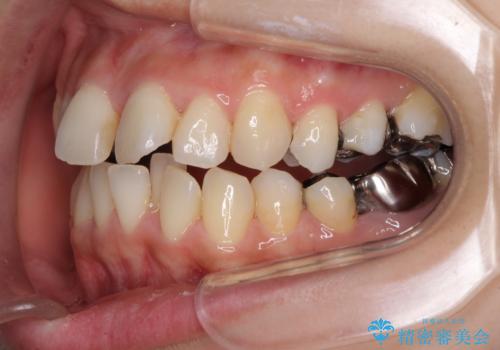

- 上下のデコボコと奥歯の咬みにくさを気にして来院された患者様です。

上顎骨の幅が下顎骨よりも小さいので、拡大装置により骨幅を広げて上下関係を改善し、その後インビザラインにて歯並びを整えることとしました。

上下の骨幅を改善したことで、スムーズに歯列矯正を行うことができました。

矯正治療中に近医で銀歯を外す治療を開始したため、治療後に奥歯の咬み合わせが不十分ですが(こちらは近医での治療により改善するとのこと)、歯列と咬み合わせが改善され、患者様には大変満足していただきました。